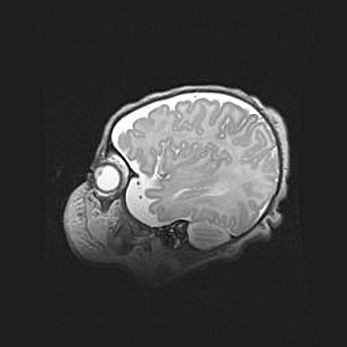

Множественные кисты обоих полушарий головного мозга, наибольшая из них в правой затылочной области. Ассиметричная атрофическая гидроцефалия.

Возраст: 7 месяцев

Вес: 5660 г

Пол: мужской

Окружность головы: 41,5 см

Срок гестации: 28-29 недель

Кисты головного мозга развиваются в результате многоочаговых некрозов вещества мозга и возникают вследствие перенесенной перинатальной инфекции, менингитов, энцефалитов, асфиксии, родовой травмы, расстройств мозгового кровообращения различного генеза. Образованию кист в веществе головного мозга плодов и новорожденных способствуют такие факторы, как высокое содержание в нем воды, недостаточная (или отсутствие) миелинизация и слабая астроглиальная реакция на повреждение.

Кисты могут сочетаться с гидроцефалией и другими поражениями головного мозга.